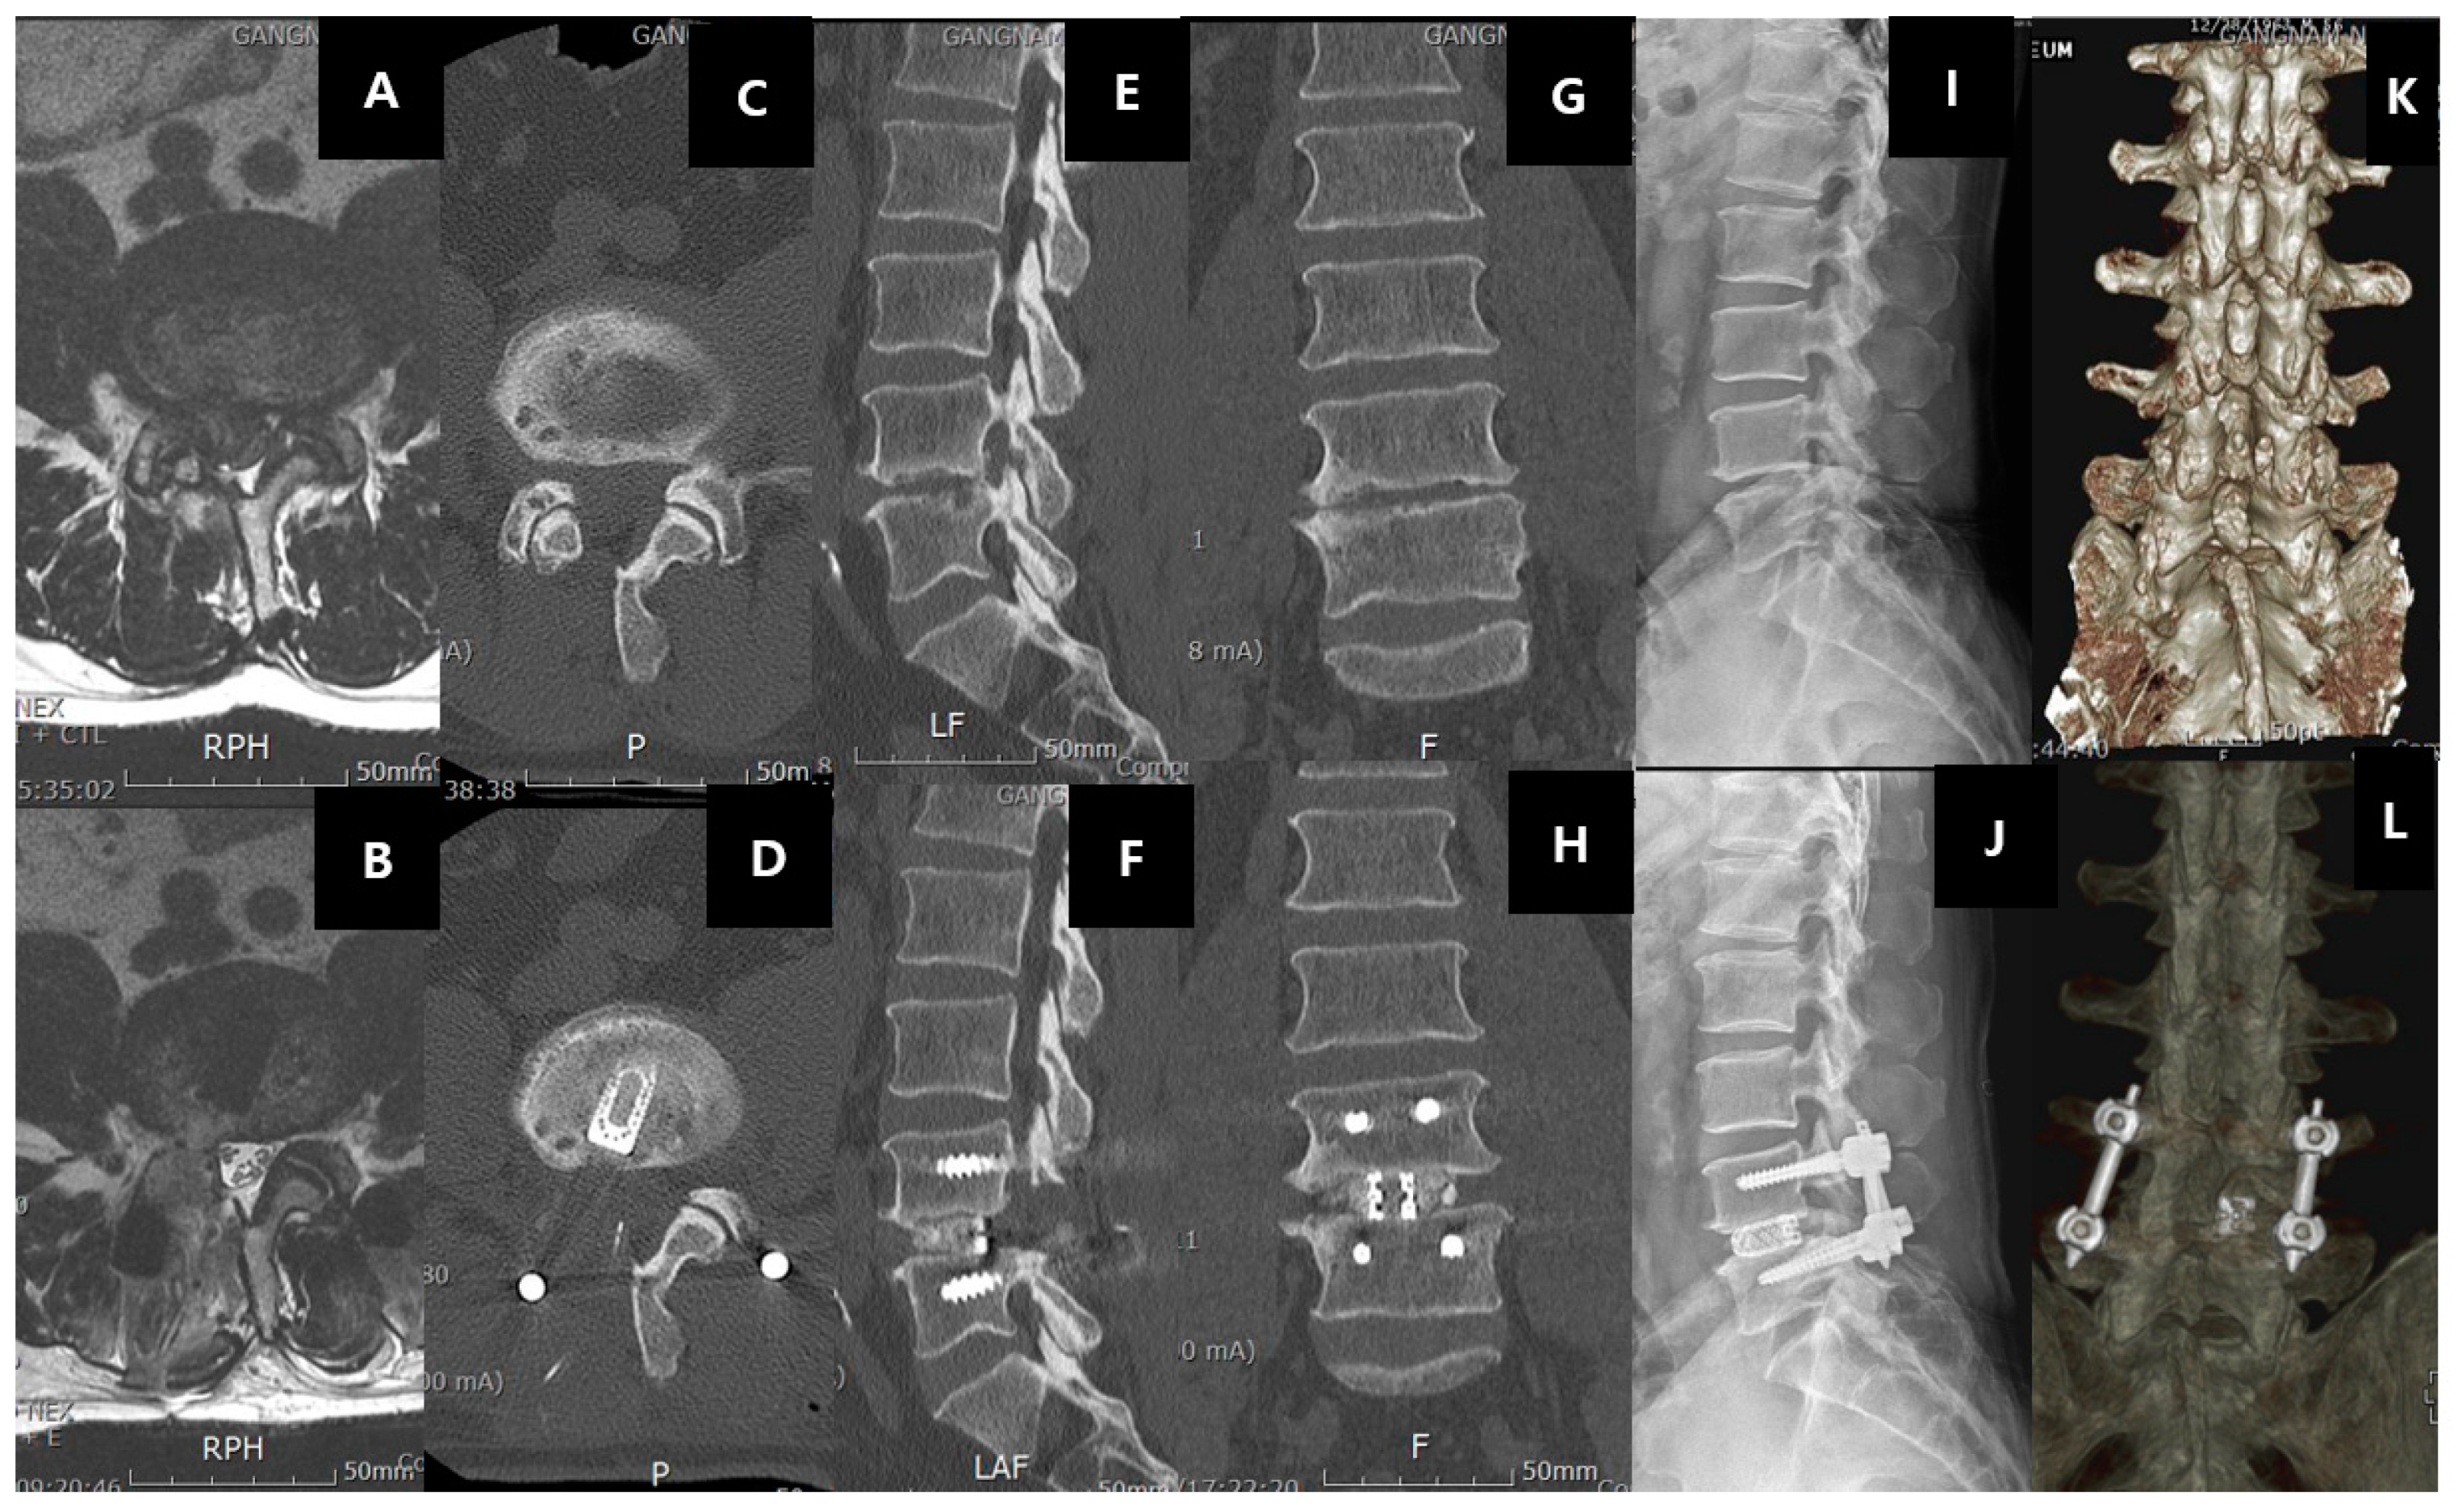

61UWIqrokYL.jpg。Autologous fibroblasts induce fibrosis of the nucleus。Intervertebral Disk Herniation。令和6年産 新米コシヒカリ 5.キロ。

。Frontiers | Intervertebral disc degeneration—Current。[A01151548]動画で見る音声障害 Ver.1 [DVD] (1) 日本音声言語医学会。[A01371176]リウマチ生活指導 (リウマチのリハビリテ-ション (第1集)) 椎野 泰明。[A01206585]泌尿器ケア 13年9月号 18ー9―泌尿器科領域のケア専門誌 泌尿器科術前・術後のケアマニュアル [単行本]。[A01438740]膠原病診療ノート―症例と文献の分析に基づく実戦的マニュアル 三森 明夫。Doctor Stories Dr.コトー診療所のモデル。[A11076679]消化器内視鏡 第24巻11号 20 これは役立つ十二指腸病変アトラス (消化器内視鏡2012年11月号) 消化器内視鏡編集委員会。[A01214448]救急医学 2012年 01月号 [雑誌]。[A11849401]非浸潤性乳管癌のすべて [単行本] 秋山 太。[A12284976]スラッター 小動物の外科手術(全2巻)